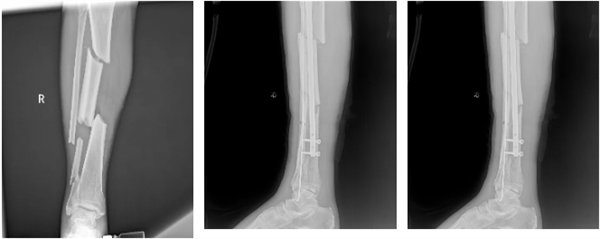

從7月29日的“右側脛腓骨下端開放性骨折閉合復位內固定術+外固定術”,到9月2日的“右下肢清創術+局部轉移皮瓣修復術+取皮植皮術”,再到9月29日的“右脛骨粉碎性骨折閉合復位+有限切開髓內針內固定術”,三次關鍵手術環環相扣、精準施策。術后,醫療團隊持續給予抗感染、消腫止痛、抗凝、促骨折愈合等綜合治療,護理團隊則從傷口護理、肢體功能訓練到營養支持全程精細化照護,用專業與溫暖陪伴患者度過艱難的康復期。